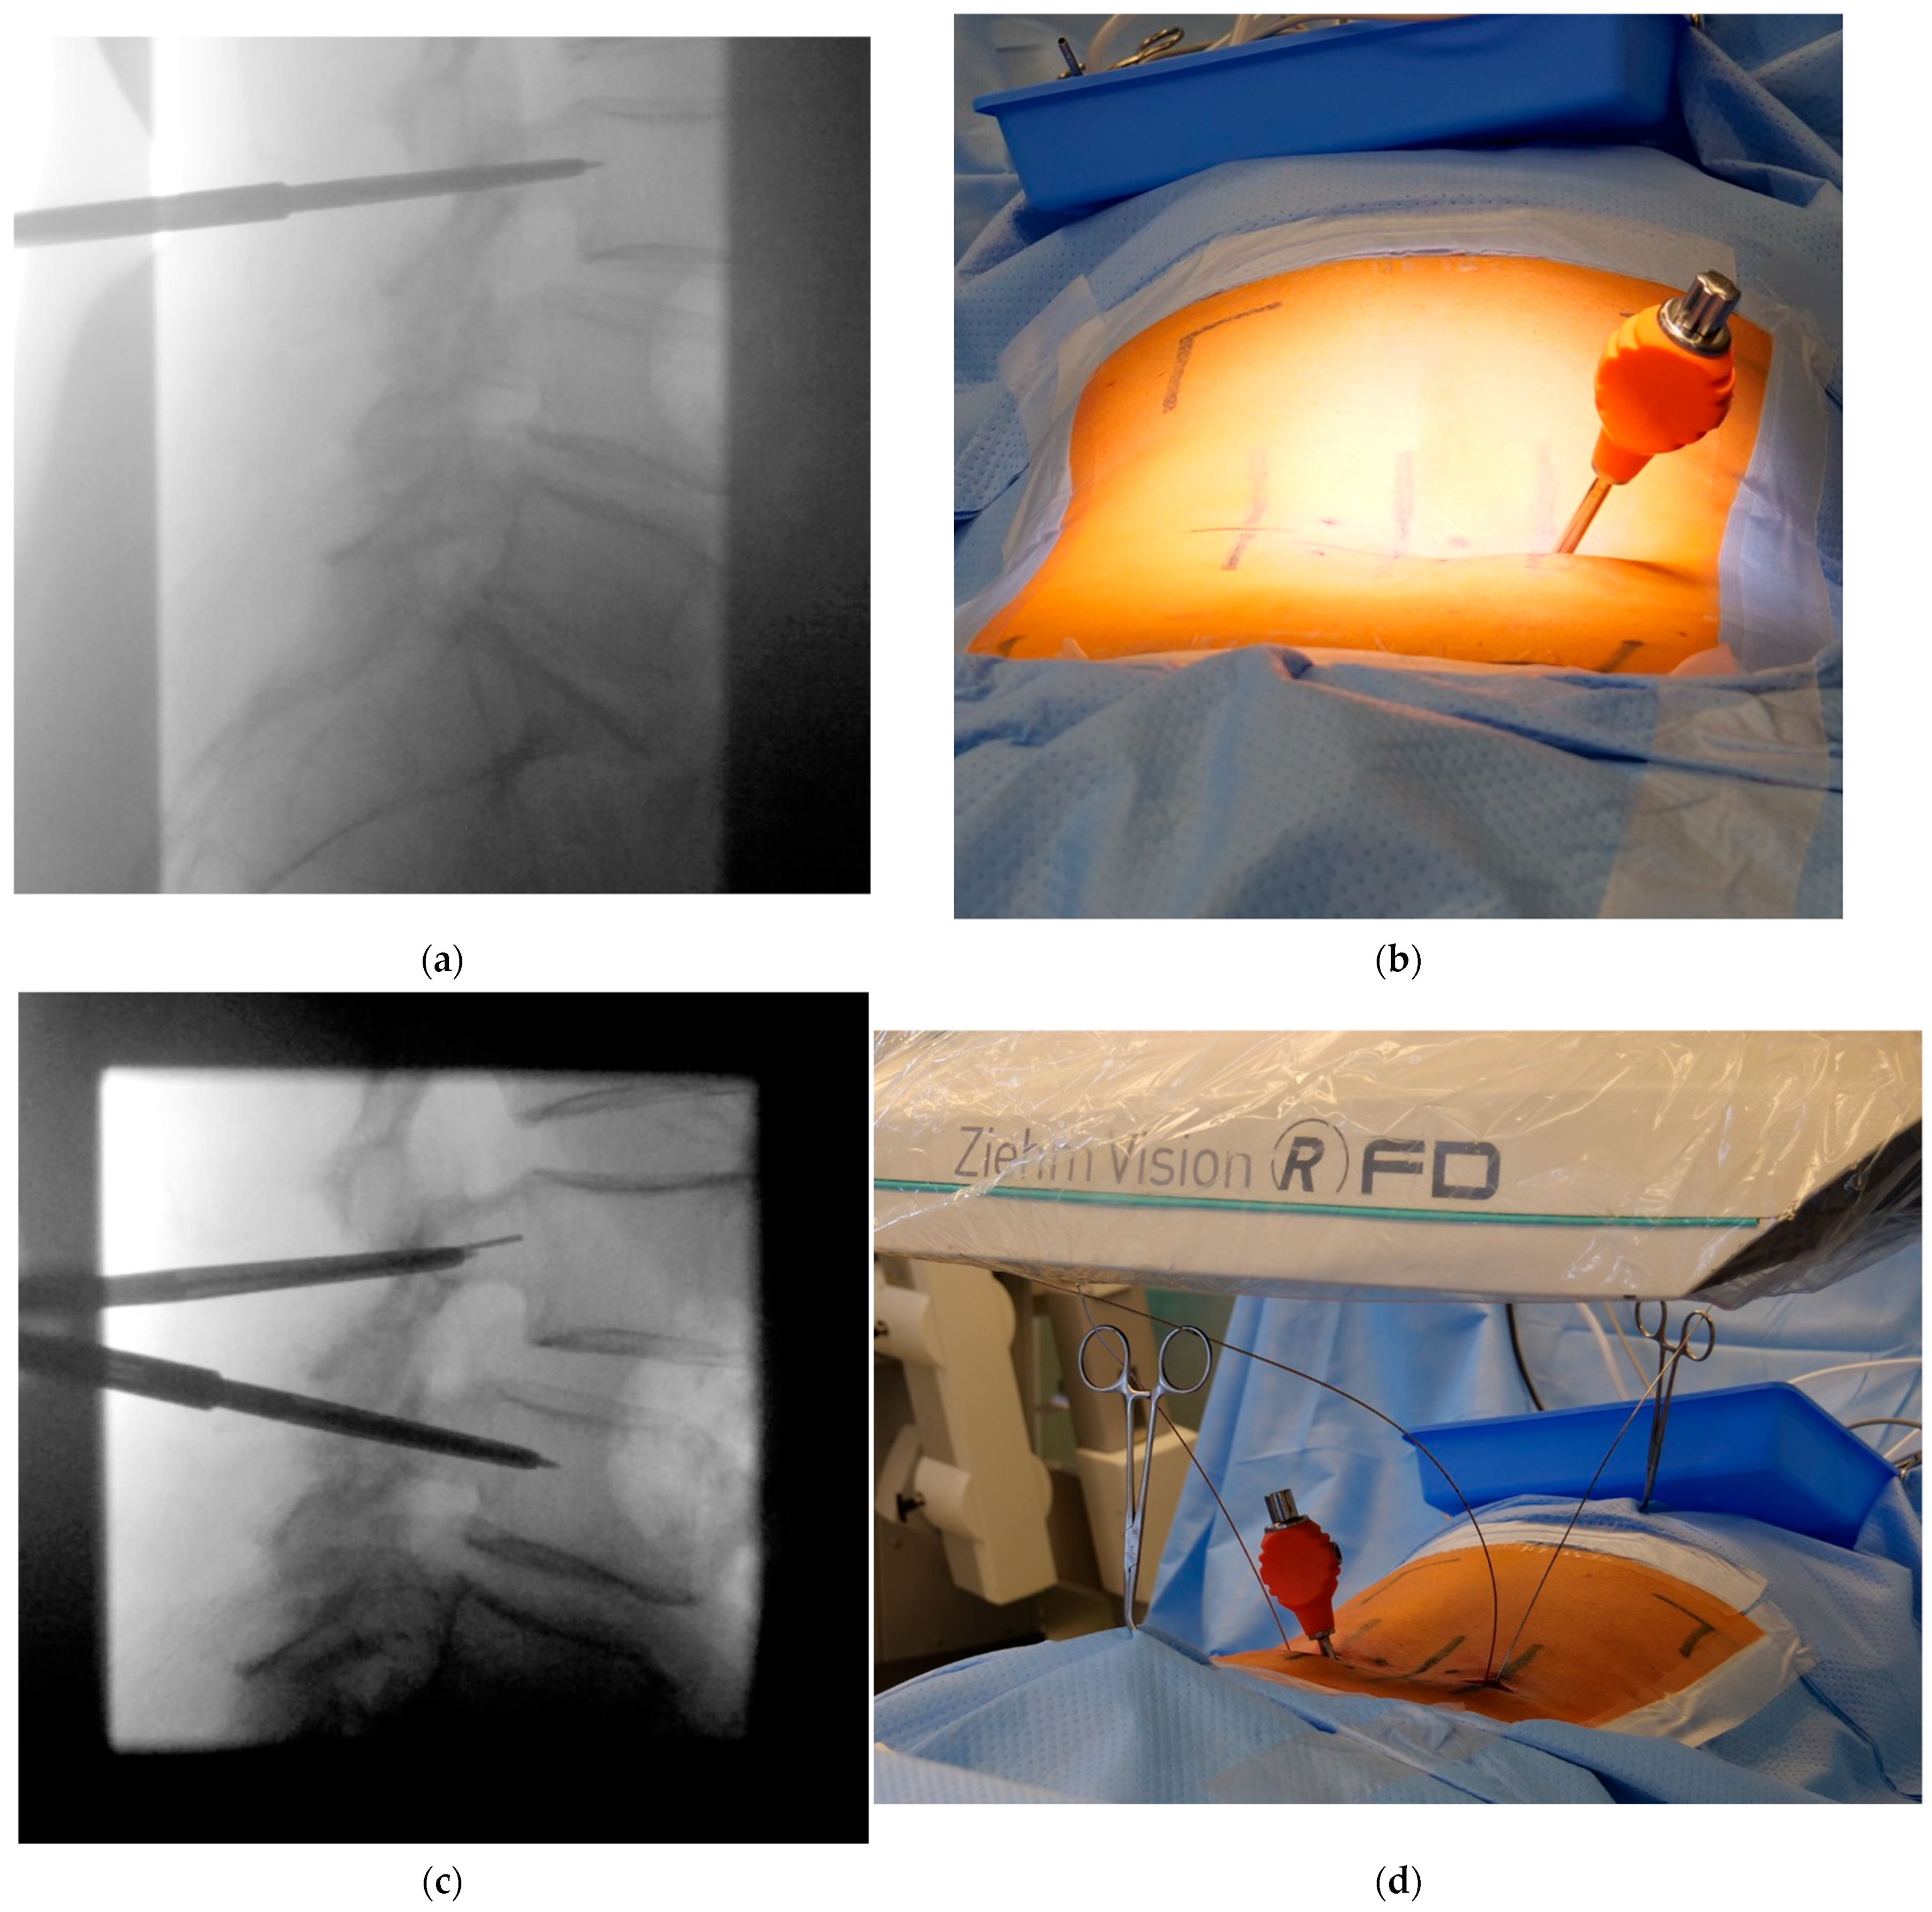

- Using a metal template for entry point identification

- Jamshidi needle positioning and K-wire placement

- Confirmation of strictly transpedicular K-wire positioning

- Ipsilateral placement of a tubular non-expandable retractor

- Pedicle screw insertion